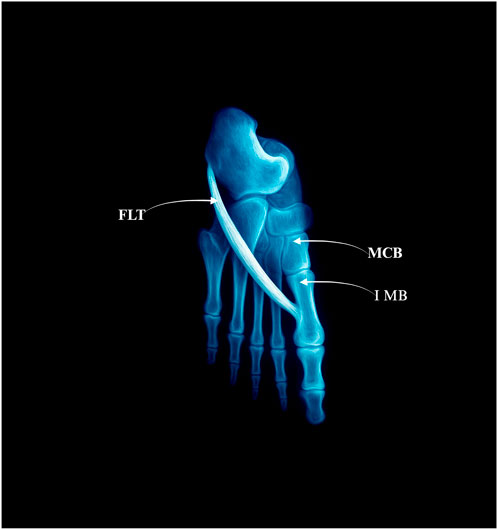

The FLT inserts solely into the lateral tubercle of the base of the first metatarsal bone–Figure 1.

Figure 1. Type I: single distal insertion to the lateral tubercle of the base of the first metatarsal. Abbreviations: FLT fibularis longus tendon; 1 MB the first metatarsal bone. MCB–medial cuneiforme bone.